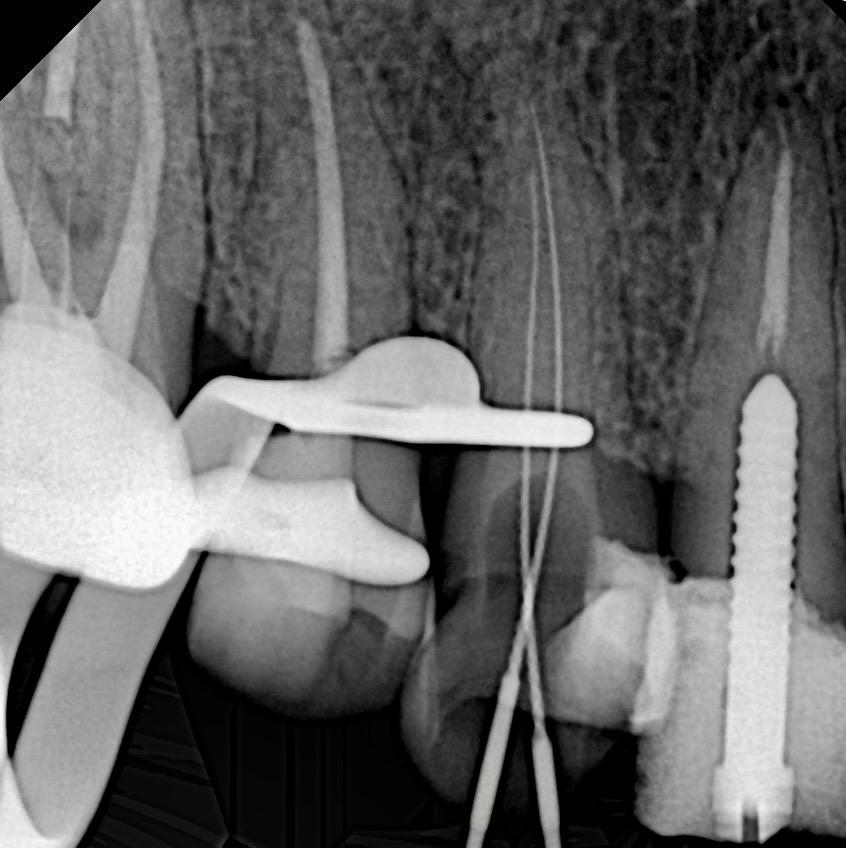

Radiographic Findings

- Previous endodontic treatment visible in UL3 and UL6

- Inadequate obturation and coronal leakage

- Widened PDL space on UL6

- Normal apical architecture on other teeth

- No sinus tract present

ENDODONTIC TREATMENT PROTOCOL

- Isolation: Achieved using full quadrant rubber dam isolation

- Canal preparation: Rotary NiTi system

- Irrigation: NaOCl + EDTA final rinse

- Obturation: Single-cone technique using resin-based Kerr sealer

- Coronal seal: SDR composite immediately post-obturation